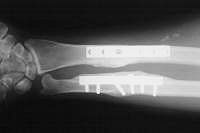

Ulnar shortening osteotomy with compression plate fixation restored satisfactory alignment.  The patient had exuberant periosteal bone growth around the side of osteotomy, but did not have evidence of delayed healing, other hardware problems, and had an excellent clinical result in terms of pain relief and recovery of motion.